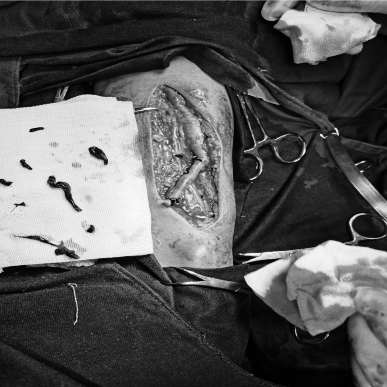

痛风是一种常见的代谢性疾病,当人体尿酸生成过多或排泄不畅,导致血液中尿酸水平升高(男性高于420μmol/L,女性高于360μmol/L),就可能形成尿酸盐结晶沉积在关节等处,引发剧烈疼痛(急性痛风性关节炎)、痛风石,甚至可能损害肾脏、引发心血管疾病等风险。 【尿酸失衡是罪魁祸首】 痛风的根源在于“尿酸代谢失衡”。人体嘌呤(来自食物和自身细胞)代谢后产生尿酸,通常由肾脏排出维持平衡。失衡后,未排出的尿酸会形成尿酸盐结晶沉积于关节、肾脏等部位,引发炎症和损伤。 高嘌呤饮食(如海鲜、动物内脏、浓汤)、饮酒(尤其啤酒)、剧烈运动、受凉、肥胖、熬夜、情绪压力等都可能是引起尿酸代谢失衡的诱因。 【管好生活方式,减少发作风险】 1.饮食上:减少高嘌呤食物摄入,可多选择蔬菜、水果、谷物、低脂奶制品等低嘌呤食物,严格控制酒精摄入,多喝水(心肾功能正常者每日 2000-3000ml),少喝含糖饮料。 2.体重管理:肥胖与痛风关联密切,通过合理饮食和适度运动逐步减重,避免过快减重。 3.运动和保暖:急性期需休息,缓解期选择游泳、散步、骑车等温和运动,减少关节冲击,并注意关节保暖,避免受凉。 【规范治疗:止痛与降尿酸并重】 ✓急性发作期:此时需要快速消炎止痛,常用药物包括非甾体抗炎药(谨遵医嘱,注意胃肠反应)、小剂量秋水仙碱、或短期糖皮质激素。请注意:急性期通常不自行加用降尿酸药。 ✓缓解期管理:长期规律降尿酸是减少复发的核心,药物需在医生指导下选择(如别嘌醇、非布司他抑制生成;苯溴马隆促进排泄,注意多饮水碱化尿液),将血尿酸持续控制在合适水平(如无痛风石者<360μmol/L,有痛风石者<300μmol/L)。切记:即使无症状,也需遵医嘱坚持服药。 【定期监测与长期坚持】 定期关注尿酸指标,初始治疗每2-4 周一次,稳定后每3个月一次,达标后每半年一次。每年筛查肾功能、尿常规等,记录发作情况,便于调整治疗方案。 【重要提醒】 痛风是可防可控的慢性病,别信偏方!通过科学的生活方式调整、规范的药物治疗和规律的监测随访,就能有效减少发作频率,保护关节和肾脏功能。 注:部分图片来源于网络,如有侵权,请联系删除。 贵州航天医院肾脏风湿科专家简介 冯远军 中共党员,肾脏风湿、肝胆外科党支部书记,肾脏风湿科主任,主任医师 临床擅长:对慢性肾脏病、急性肾损伤、急慢性肾小球肾炎、肾病综合症、风湿性疾病、间质性肾炎、肾小管损伤等疾病的诊治及血液透析技术、动静脉内瘘成形术及疑难病例的诊治具有丰富的临床经验。 曾在上海市第一人民医院及贵阳市第一人民医院进修学习,贵州省医学会肾脏病学分会第五届委员会委员,遵义市医学会肾脏病学分会第一届委员会副主任委员,遵义市医学会风湿病学分会第一届委员会副主任委员,荣获“贵州航天劳动模范、遵义市汇川区先进工作者”,遵义市医疗事故鉴定专家库成员,主持省市级科研项目4项,完成4项,近5年发表论文10余篇,北大核心期刊1篇。 王卫华 肾脏风湿科主任医师 临床擅长:从事临床工作28年,擅长尿毒症患者血管通路的建设及维护(如标准和高位动静脉内瘘术、取栓+内瘘重建术、内瘘狭窄球囊扩张术、长期中心静脉置管术及肾穿刺活检术)等手术,对原发性和继发性肾病综合征、急、慢性肾小球肾炎、慢性肾脏病、泌尿系感染、结缔组织病、急性中毒、痛风、贫血、血小板减少症等疾病诊治及血液透析技术应用等具有丰富的临床经验。 1995年毕业于遵义医学院临床医学系,曾前往重庆医科大学进修学习肾脏疾病及血液净化;遵义市医学会肾脏病学分会常务委员,遵义市血液净化质量控制中心委员;先后发表肾病专业省部级医学刊物医学论文8篇,主持市级科研项目2项。 李丽华 中共党员,肾脏风湿科副主任医师 临床擅长:从事临床工作17年,对慢性肾脏病、急性肾损伤、急慢性肾小球肾炎、肾病综合征、风湿性疾病、间质性肾炎、肾小管损伤、急慢性肾衰竭的血液透析、CRRT治疗以及血管通路的建设维护等具有丰富的临床诊疗经验。 2006年毕业于遵义医学院临床专业,曾在遵义医学院附属医院完成住院医生规范化培养,并前往第三军医大学新桥医院、珠海市人民医院进修学习;中华医学会遵义市肾脏病学分会委员,遵义中医药学会肾病专业委员会委员,遵义市血液净化质量控制中心委员,遵义市医学会血液学分会委员会委员;发表省部级医学刊物医学论文4篇,主持参与省级科研课题1项,主持参与市级科研课题1项,院级新技术6项,获得本专业授权实用新型专利3项。 李 玫 中共党员,肾脏风湿科副主任医师 临床擅长:从事临床工作15年,对慢性肾脏病、急性肾损伤、急慢性肾小球肾炎、肾病综合征、风湿性疾病、间质性肾炎、肾小管损伤等疾病的诊治具有丰富的临床经验,擅长血液透析技术、动静脉内瘘成形术等。 2008年毕业于遵义医学院临床医学系,曾前往遵义医学院附属医院进修学习肾脏病与血液净化相关技术;遵义市医学会肾脏病学分会委员,发表肾病专业省部级医学刊物医学论文4篇。 贵州航天医院肾脏风湿科简介 基本情况 贵州航天医院肾脏风湿科2017年建立,住院患者承载能力达到50人左右,透析治疗服务惠及250余人的患者群体,在学科建设、高端医疗设备引进及专业技术队伍已达到区域内领先水平。科室共有医护人员46名,副高级以上专家7名,亚专业设置齐全,涵盖肾脏疾病、风湿免疫疾病药物治疗、透析治疗及透析通路维护等多个专业领域,为患者提供全面、精准、高效的诊疗服务。配备了尖端的医疗设备与智能化的辅助系统,包括透析机、CRRT机等设备。 专科特色 (一)肾脏病治疗领域:专精于血液透析、血液透析滤过、血液灌流、血浆置换、CRRT等尖端技术,致力于为患者量身打造个性化的肾脏替代治疗方案。 (二)在风湿病治疗方面:凭借生物制剂、免疫抑制剂等前沿药物,结合患者的具体情况,精心策划个体化的治疗策略,有效减轻患者症状,显著提升生活质量。 超声引导下球囊扩张术:内瘘狭窄是内瘘最常见的并发症之一,我们采用先进的超声引导下球囊扩张术,通过微创方式恢复内瘘通畅,有效避免了传统手术带来的创伤和痛苦。 内瘘血栓溶栓治疗、取栓术:血栓形成是内瘘功能丧失的主要原因之一,根据患者具体情况,采用溶栓治疗、取栓术等多种手段,确保患者及时恢复透析治疗。 内瘘动脉瘤形成治疗:动脉瘤是由于内瘘局部血流动力学改变引起的血管扩张性疾病,采取佩戴弹力绷带、手术修复等措施,防止动脉瘤进一步发展和破裂。 内瘘感染治疗:内瘘感染是内瘘并发症中最为严重的类型之一,一般采用敏感抗生素进行抗感染治疗,严重者采取手术清创等措施。 内瘘窃血综合征治疗:是由于内瘘建立后,远端肢体血流减少引起的一系列症状,通过调整透析方案、改善内瘘血流分布及必要时重建内瘘等措施,有效缓解患者的症状并提高其生活质量。 诊疗范围 擅长治疗急慢性肾炎、肾病综合征、肾衰竭等肾脏疾病;擅长治疗类风湿关节炎、系统性红斑狼疮、干燥综合征等风湿免疫性疾病,并为患者提供健康教育与康复指导,帮助患者更好地管理疾病,提高生活质量。 END